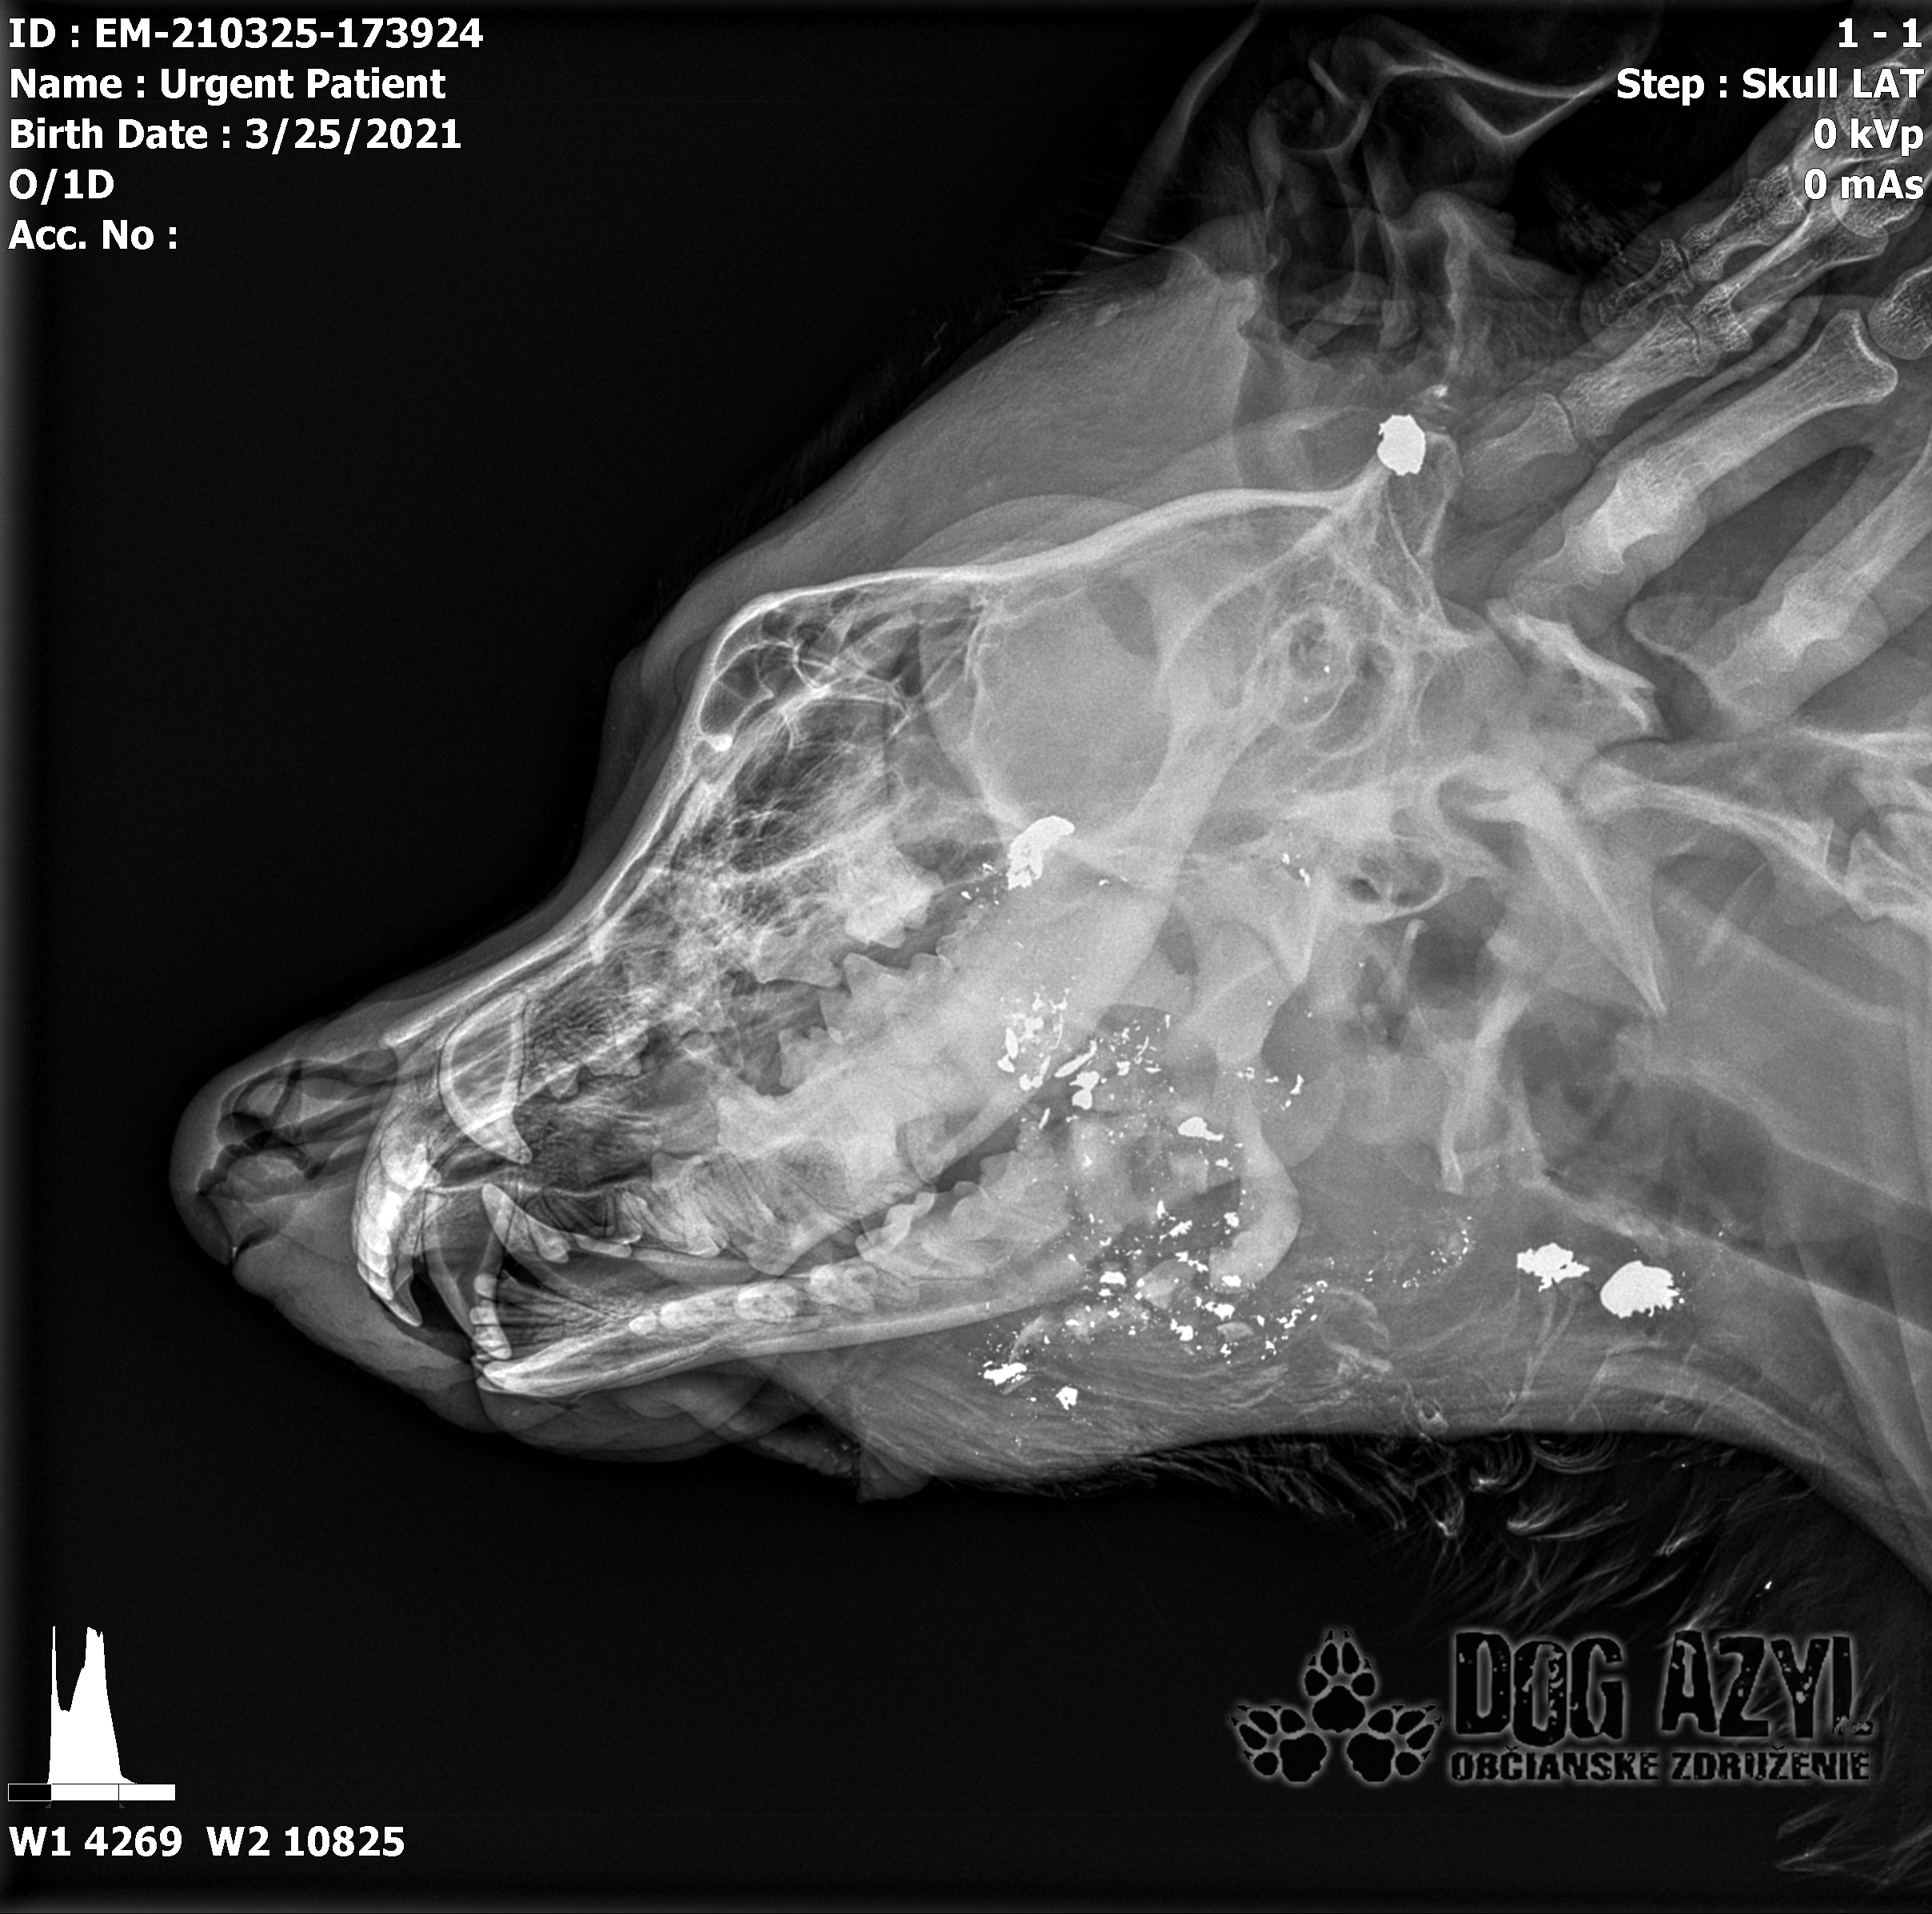

Strela zasiahla Barisa v oblasti lícnej kosti, ktorá mu rozdrvila sánku a následne putovala cez krk až po krčnú chrbticu. Úlomky z guľky (neviem ako sa to odborne volá) sa roztrieštili na "milión" kusov počas svojej cesty. Tieto úlomky sú všade (ako vidieť aj na RTG). Jeden (alebo niekoľko týchto úlomkov) sa dostali až po miechu, ale našťastie ju neprerazili. Toto spôsobilo, že Baris citlivosť v nohách na ľavej strane sice má, ale má poškodenú motoriku. Tieto úlomky sa z oblasti stavcov, miechy aj krku dnes odstránili, ale Barisko z ďaleka nemá vyhraté. Miecha je totiž zakrvácaná (opäť sa ospravedlňujem za nepresnosť a laickosť) a to, že ako veľmi je poškodená, alebo či jeho slabosť bola spôsobená "iba opuchom" sa ukáže cca do 24 hodín. Ak Baris nedajbože do zajtra stratí citlivosť v nohách, tak.. žiaľ... Ale! ak citlivosť zostane, prípadne nastane aj zlepšenie, tak vzplanie plamienok ďalšej nádeje a bojujeme ďalej!